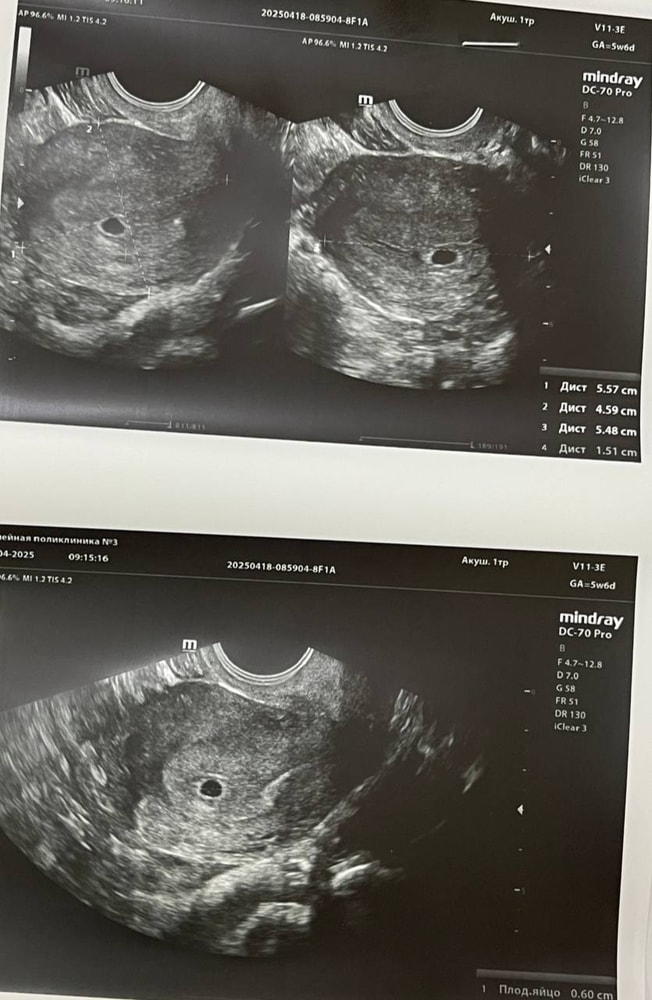

Ошибка лаборатории Инвитро. Получила новый анализ ХГЧ и сделала УЗИ.

Эмбриончика пока не видно, гинеколог поставила нам срок 4-5 недель.

Сказала приходить только через 2 недели, чтобы сразу если что и сердцебиение услышать.

Так как пару дней назад у меня была коричневая мазня и в целом уже три дня снова спустя некоторое время у меня начало потягивать низ живота выписала утрожестан вагинально и половой покой пока что.